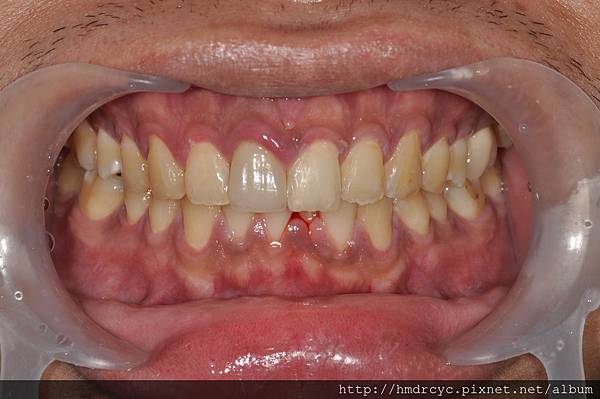

但也不是所有牙痛都不能拔除

像蛀牙引起的疼痛

通常沒有過度感染與化膿

當牙齒沒有功能價值

可以直接拔除